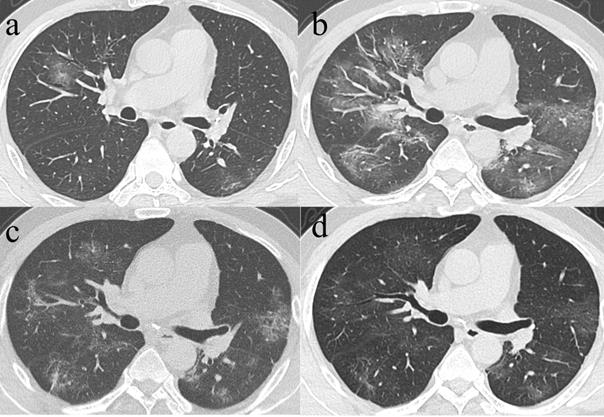

Figure 5

Series CT scans in a 65-year-old man with COVID-19 pneumonia. a. Scan obtained on illness days 4 showed consolidation affected in both lower lobes. b. Scan obtained on illness days 18 showed consolidation with an increased extent. c. Scan obtained on illness days 27 showed a predominantly mixed pattern with bandlike consolidation and parenchymal bands in both lower lobes. d. Scan obtained on illness days 36 showed a predominantly reticular pattern with interlacing line shadows mainly in both lower lobes. The patient was discharged on illness days 39.